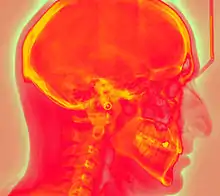

Photostimulated luminescence (PSL) is the release of stored energy within a phosphor by stimulation with visible light, to produce a luminescent signal. X-rays may induce such an energy storage. A plate based on this mechanism is called a photostimulable phosphor (PSP) plate and is one type of X-ray detector used in projectional radiography. Creating an image requires illuminating the plate twice: the first exposure, to the radiation of interest, "writes" the image, and a later, second illumination (typically by a visible-wavelength laser) "reads" the image. The device to read such a plate is known as a phosphorimager (occasionally spelled phosphoimager, perhaps reflecting its common application in molecular biology for detecting radiolabeled phosphorylated proteins and nucleic acids).

Projectional radiography using a photostimulable phosphor plate as an X-ray detector can be called "phosphor plate radiography"[1] or "computed radiography"[2] (not to be confused with computed tomography which uses computer processing to convert multiple projectional radiographies to a 3D image).

In phosphor plate radiography, the imaging plate is housed in a special cassette and placed under the body part or object to be examined and the x-ray exposure is made. The imaging plate is then run through a special laser scanner, or CR reader, that reads and converts the image to a digital radiograph. The digital image can then be viewed and enhanced using software that has functions very similar to other conventional digital image-processing software, such as contrast, brightness, filtration and zoom. CR imaging plates (IPs) can be retrofitted to existing exam rooms and used in multiple x-ray sites since IPs are processed through a CR reader (scanner) that can be shared between multiple exam rooms.[6]